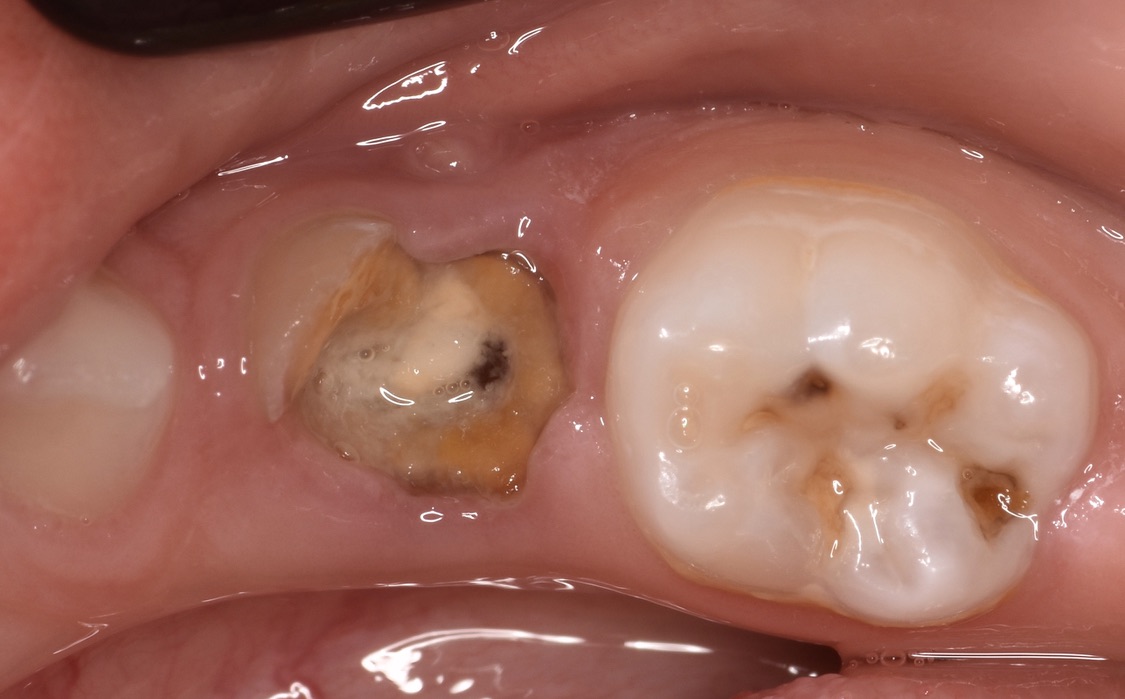

Presencia de lesiones de caries dental en muelas de leche

El consumo frecuente de azúcares a partir de panela, achocolatados, galletas, gomas, tortas, gaseosas, jugos artificiales en botella o en cajita y snacks, sumados a prácticas de higiene bucal insuficientes o inadecuadas se relacionan directamente con caries dental. Estos hábitos favorecen el acúmulo de placa dentobacteriana sobre los dientes y hace que con el tiempo se desarrollen lesiones de caries dental. Por otro lado, existen grupos especiales que tienden a desarrollar más facilmente lesiones de caries dental, como por ejemplo: bebés entre los 12 y 30 meses (conocida como caries del biberón, caries rampante o caries de la infancia temprana); niños entre los 6-7 años de edad (tiempo en el que aparece el primer molar permanente o la muela de los 6 años); pacientes con ortodoncia o aparatología ortopédica fija o removible; pacientes que sufren de “boca seca” asociado a medicamentos, enfermedades o radicación en cabeza y cuello; pacientes con necesidades especiales y pacientes con dificultades motoras. La caries dental no solo afecta al esmalte dental, sino también a la dentina, al cemento y en consecuencia, a la raíz de los dientes.